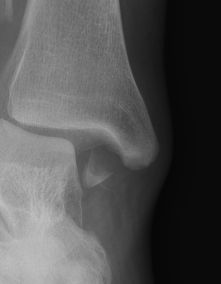

![]() |